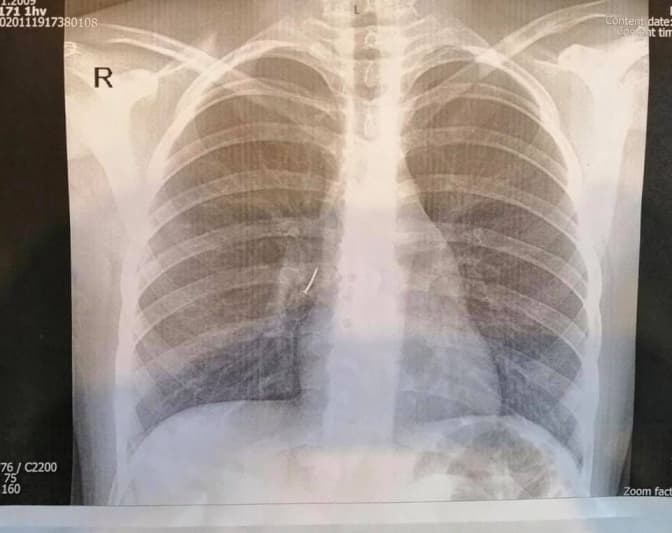

Цвях застряг у бронхах, дитину терміново прооперували.Оперував дитину дитячий хірург Олександр Колодій.

«З правого проміжного бронха дитини ми дістали канцелярський цвях з пластмасовою частиною і гострим вістрям. То було непросто, адже пластмасова частина цвяха повністю перекрила бронх так, що нижня доля правої легені майже не функціонувала», – розповів лікар.